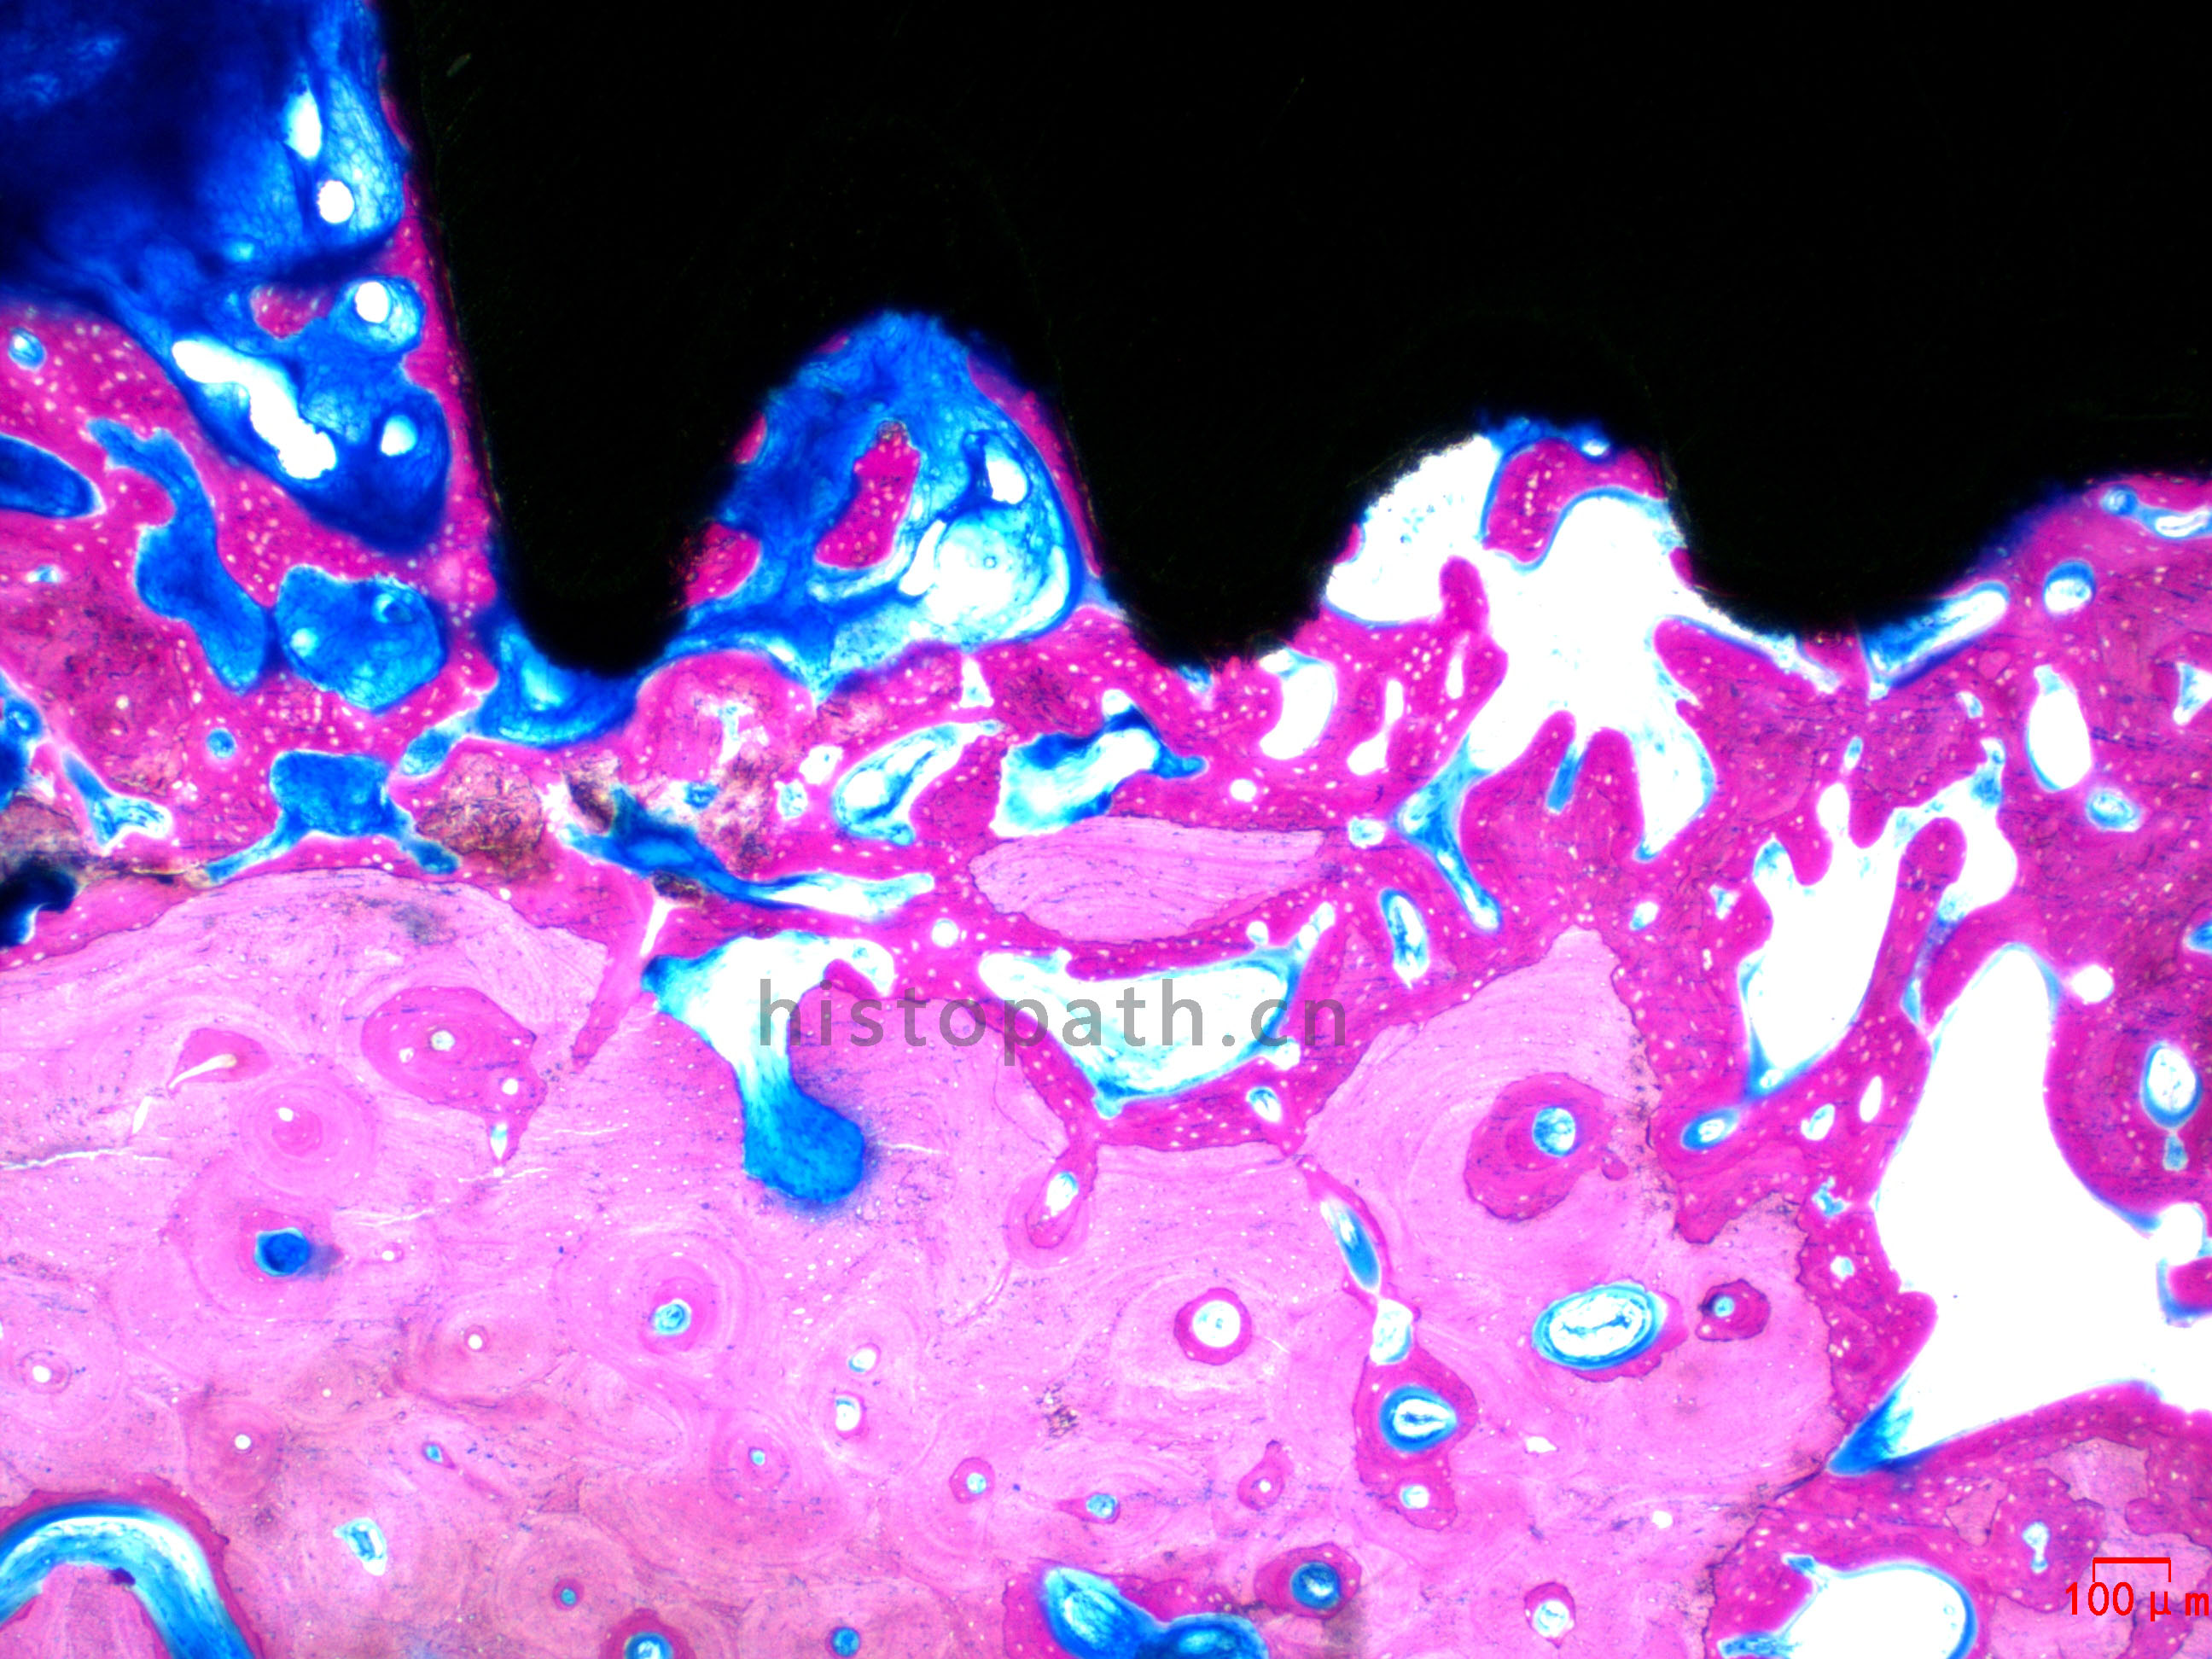

牙体种植:甲苯胺蓝染色

牙种植体甲苯胺蓝染色.jpg

使用德国EXAKT切磨系统进行硬组织切片,特别是对于含有金属这类植入物的组织,是一种精确的组织切片技术。

各类尺寸的含金属植入物骨、牙齿、血管等硬组织样本脱水,7200树脂浸润包埋,后期用标准尺寸(25mm*75mm)的树脂片进行切磨片处理。

将包埋好的硬组织树脂块,用EXAKT 硬组织切片机先切一个200um的厚片,然后再通过EXAKT 硬组织磨片机将其磨到20-30um薄片,样本是已经硬组织包埋好的含金属的动物样本。

针对不同的病理阅片指标需求,行HE染色、Masson染色、亚甲基蓝-酸性品红染色、VG染色、Movat染色等。